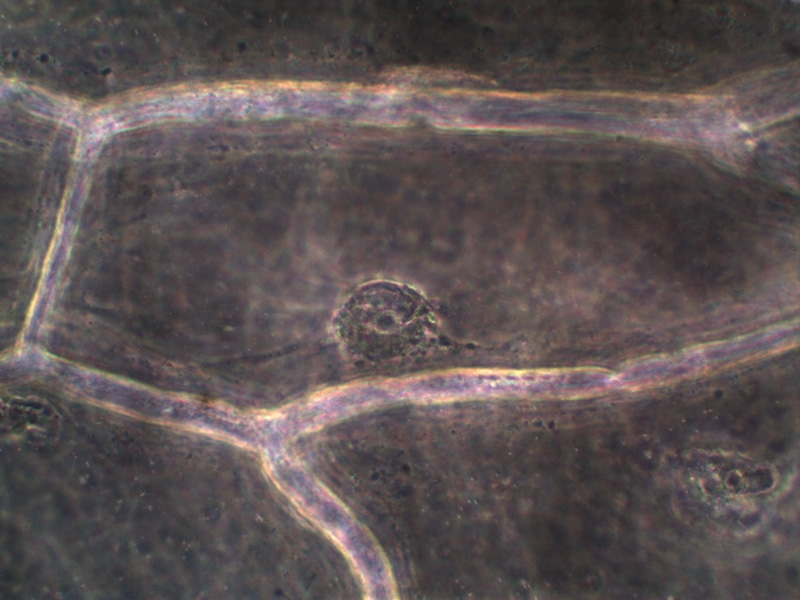

Набор для наблюдений методом позитивного фазового контраста для микроскопов DO Genetic Pro/DO Evolution 100. Применение: исследования живых клеток и их составляющих; в микробиологии и бактериологии, цитологии, гистологии, гематологии, и тому подобное. Может использоваться в биологических и медицинских институтах, клинических лабораториях, санэпидстанциях и других научных организациях.